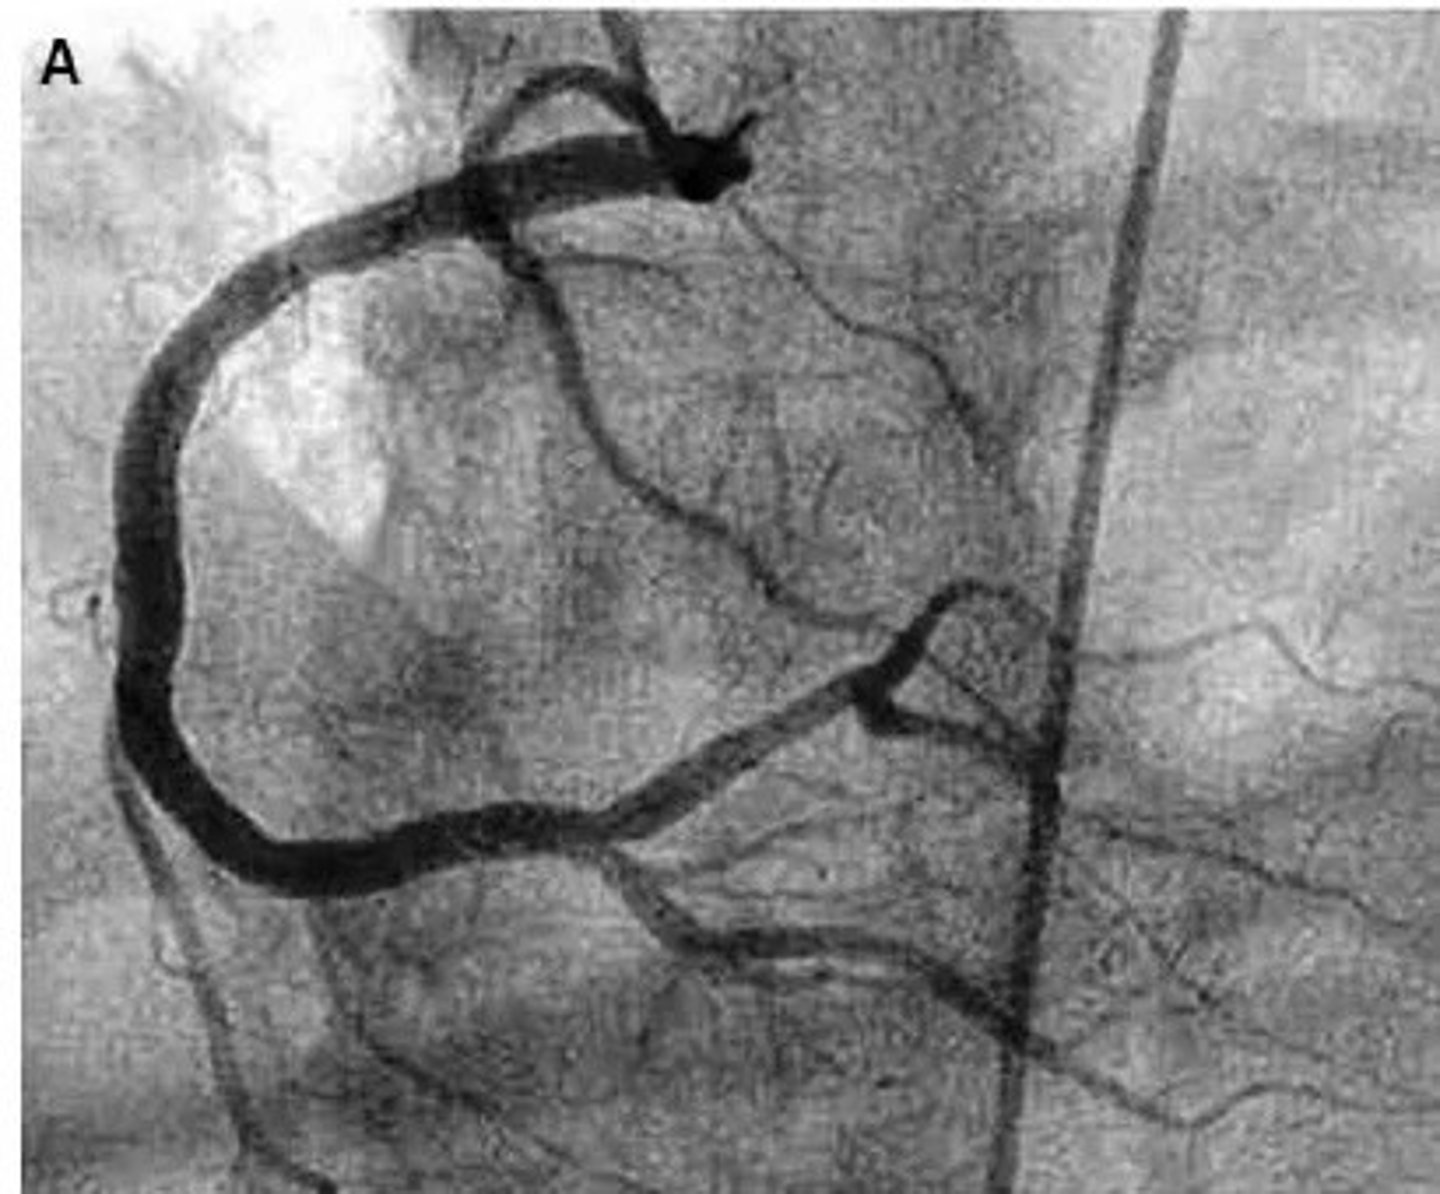

left coronary artery angiogram

what pathology is present?